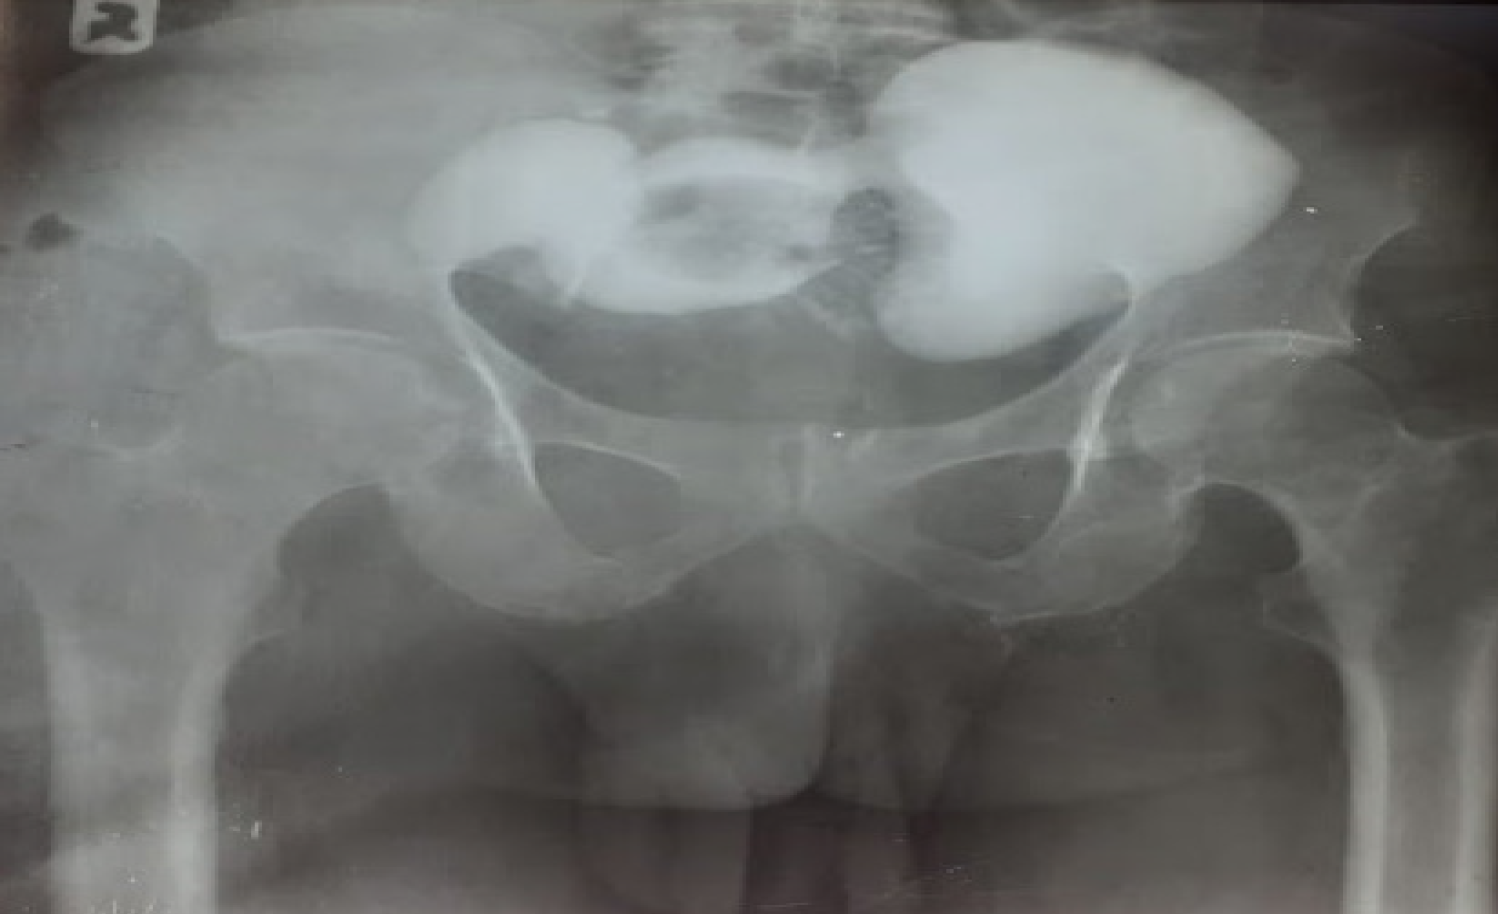

Figure 3

A cystogram of the patient in Figure 1 shows the bladder with the filling defect of the urethral catheter balloon and bladder diverticula.